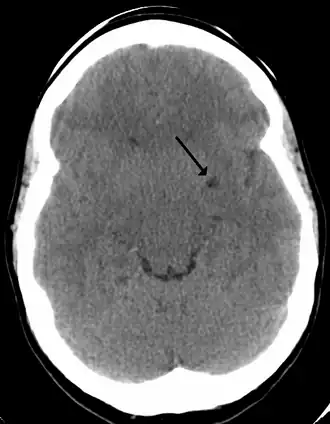

A perivascular space as seen on CT